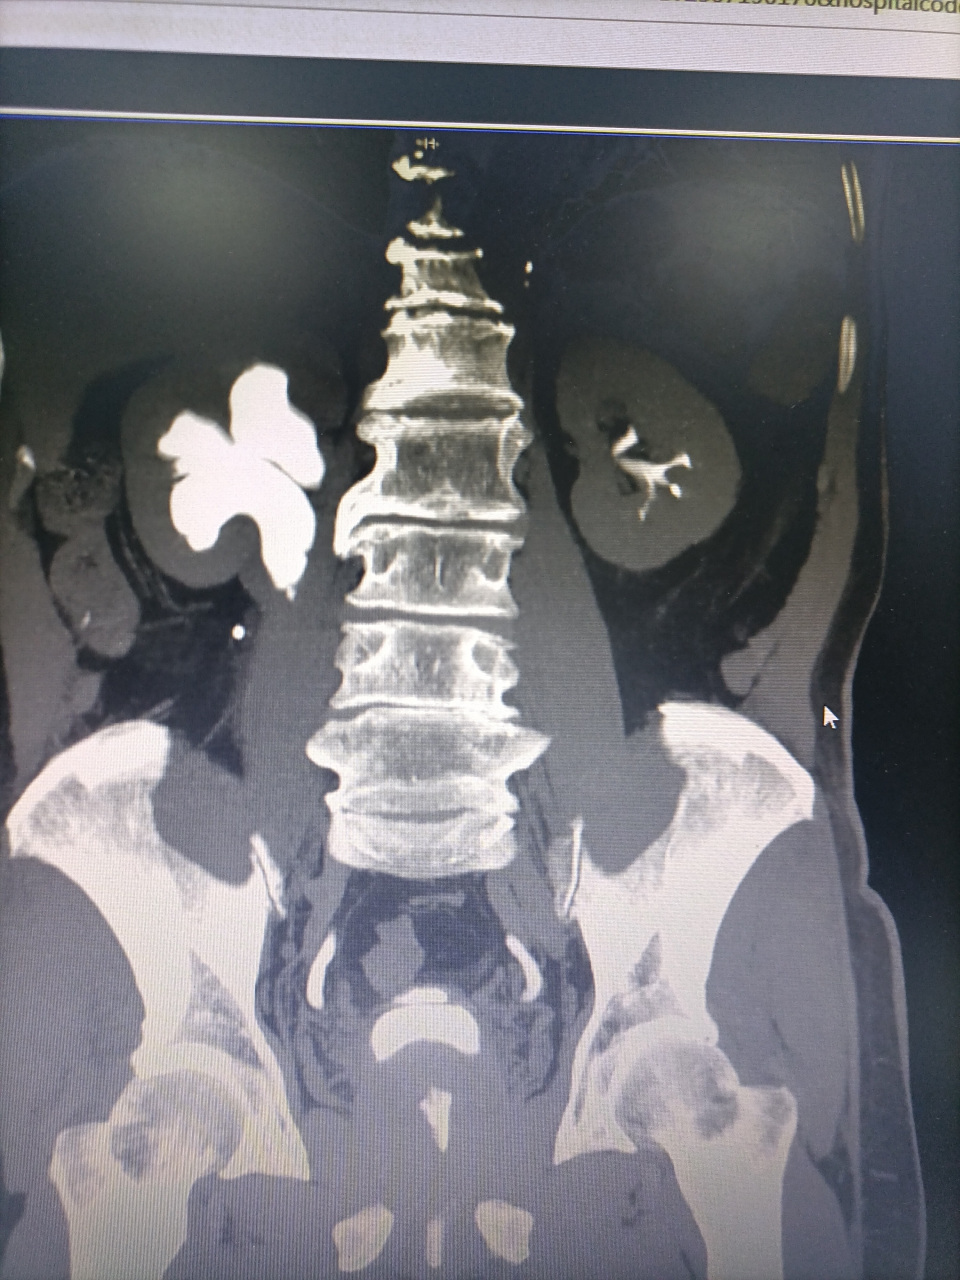

双侧双肾盂双输尿管畸形

双肾盂 / 双输尿管畸形 double pelvic / double ureter肾母细胞瘤